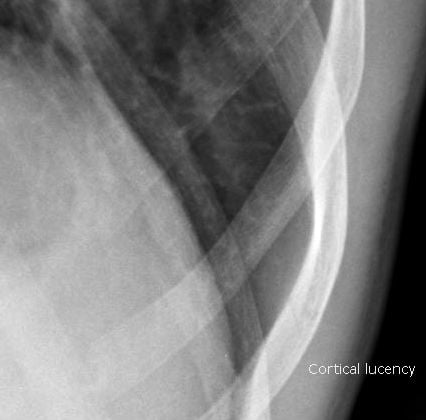

Figure 2:

Magnified image showing subtle cortical lucency of the lower rib suggesting fracture.